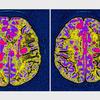

Avtoimuna bolezen, ki povzroča vnetje v osrednjem živčevju.

Za multiplo sklerozo (MS) v glavnem zbolevajo ljudje v najaktivnejše obdobju življenja, od dvajsetega do štiridesetega leta starosti. Gre za najpogostejše nevrološko obolenje za katerega ne poznamo ne vzroka in ne zdravila. Je bolezen centralnega živčnega sistema in je najštevilčnejša bolezen nevro imunskega sistema pri nas.

MS v devetdesetih odstotkih povzroča težko in najtežjo invalidnost, je neozdravljiva, zato bolnikom ostane le blažitev težav, ki so posledica že nastalih okvar in poškodb.

Svetovni dan multiple skleroze, 30. maj, letos poteka pod geslom Povežimo se. Mednarodna zveza za multiplo sklerozo s sedežem v Londonu želi s svetovnim dnevom, povečati ozaveščanje o tej avtoimuni bolezni, ki povzroča vnetje v osrednjem živčevju.